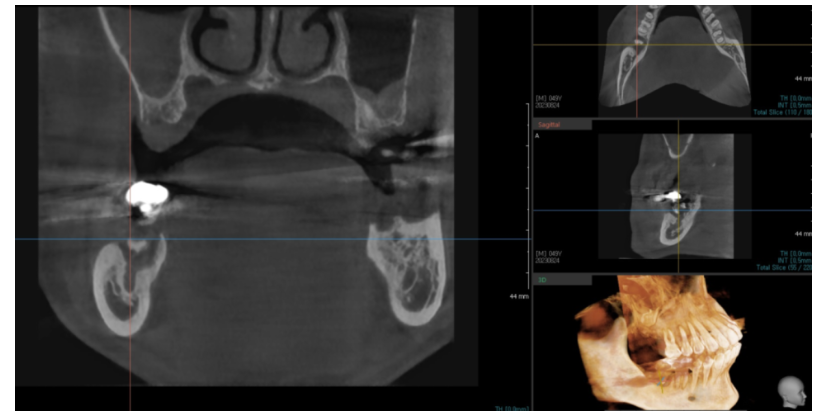

네비게이션 임플란트 수술 방식도 한몫 하죠

x-ray 만 찍어봐도 뼈 상태를 미리 정확하게 확인할 수 있고,

정밀한 각도와 위치로 식립이 가능해졌기 때문에

조건만 맞으면 발치 직후 바로 심는 것이 안정적인 치료법이 되었습니다.

230824 ct를 찍고 수술 시기가 결정됩니다!

<뼈 상태가 좋지 않아 10개월 기다린 환자분 케이스>

그만큼 당일 식립은 정확한 진단과

고도의 기술력이 뒷받침 되어야 합니다.